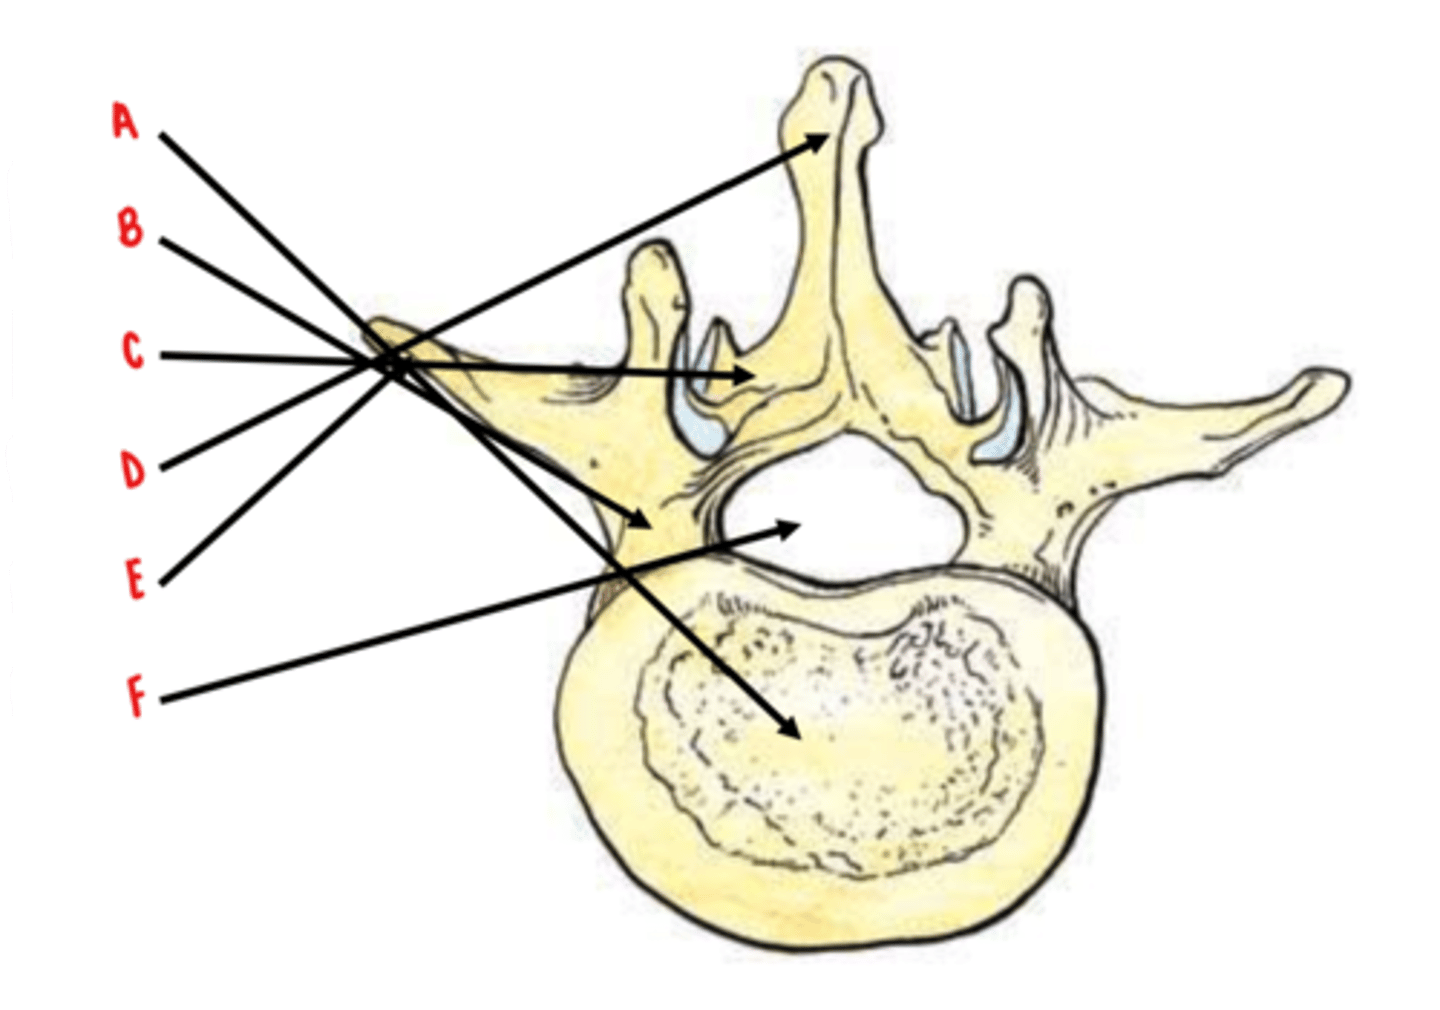

50 Terms

body

Identify A

pedicles

Identify B

laminae

Identify C

spinous process

Identify D

transverse process

Identify E

vertebral foramen

Identify F